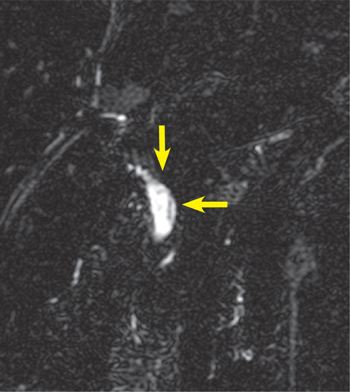

Huỳnh Hồng Quang (2010) cũng đã báo cáo một bệnh nhân nam 42 tuổi tại Quảng Nam nhiễm Fasciola sp. lạc chỗ gây xuyên thủng đường mật, xuất huyết rỉ rả và cần can thiệp nội soi mật tụy ngược dòng, gắp sán ra kết hợp với điều trị nội bằng triclabendazole, nhưng không cầm máu hẳn nên bác sĩ phải mổ hở để giải quyết. Chụp MRI sau 3 tháng điều trị không còn thấy vệt sán cũng như chít hẹp hoặc các thương tổn nhu mô gan mới do sán Fasciola sp. gây ra.